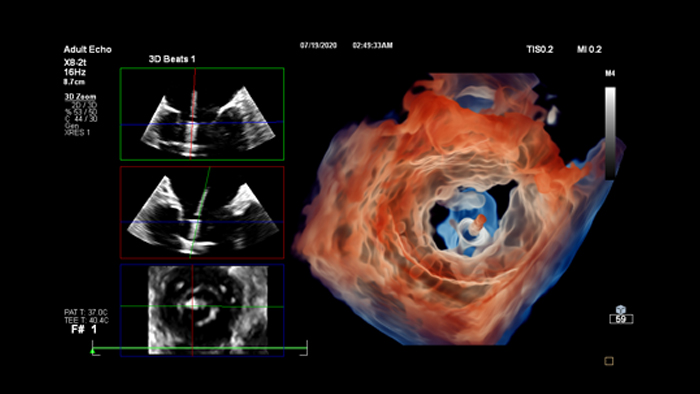

Enhance diagnosis confidence and clinical efficiency through superior image quality, advanced quantification tool and automation technology.

Review, analyze and quantify clinical information from different modalities and for various clinical indications with AI-enabled 3D models, maps and other quantitative tools.